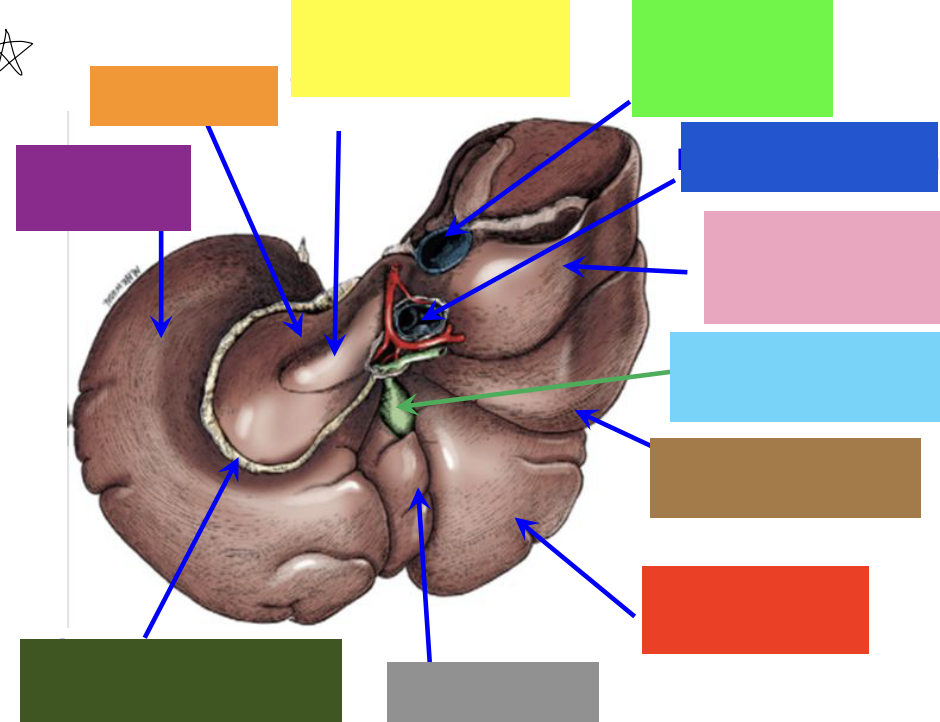

purple box

left lateral lobe

orange box

caudate lobe

yellow box

papillary process of the caudate lobe

neon green box

right lateral lobe

dark blue box

hepatic portal vein

pink box

caudate process of the caudate lobe

light blue box

gall bladder

brown box

right lateral lobe

red box

right medial lobe

grey box

quadrate lobe

dark green box

lesser omentum